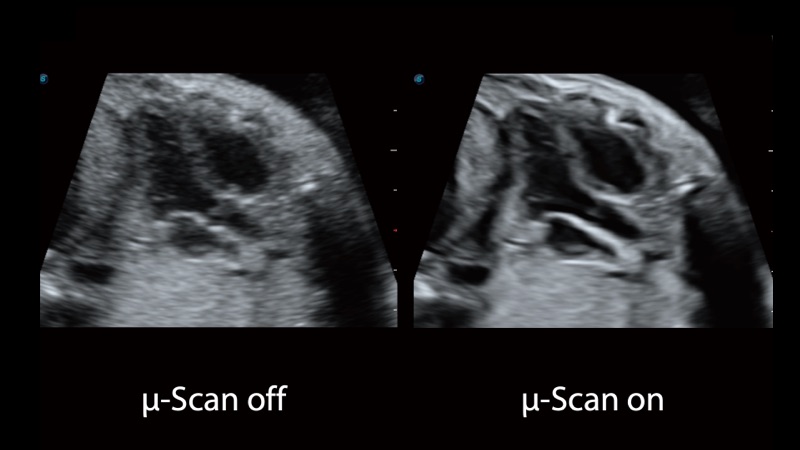

開立醫(yī)療通過不斷的技術(shù)創(chuàng)新,為大眾的生命健康提供持續(xù)關(guān)愛。P12 Plus采用全新一代超聲成像平臺(tái),新平臺(tái)旨在將真實(shí)還原組織解剖結(jié)構(gòu)作為首要目標(biāo)。平臺(tái)采用全新集成化硬件模塊,搭載新一代芯片,系統(tǒng)性能得到大幅提升,為您的診斷提供了豐富的臨床信息。優(yōu)異的圖像表現(xiàn),豐富的探頭配置,全面的應(yīng)用功能,為您日常診斷提供了可靠的助手。